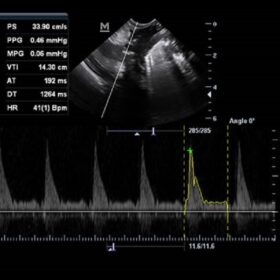

Ultrasound Mindray Z60 – Image Gallery

- IMT (Intima-Media Thickness) Auto measurement of anterior and posterior wall thickness providing accurate carotid status.